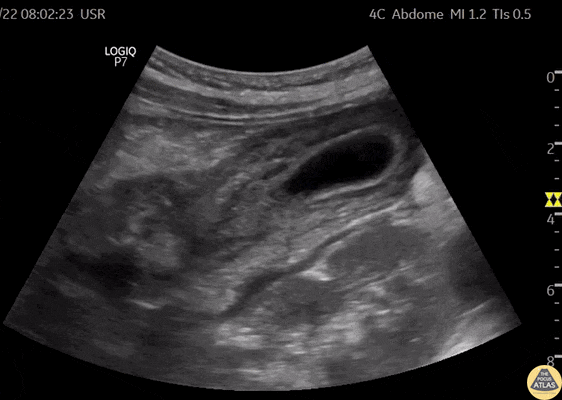

Biliary - Thick Walled Gallbladder in Dengue Fever (Long Axis) [1/2]

A 28 year old female comes to the ER with fever, myalgia, hypotension, and abdominal pain. This case illustrates one of the ultrasound findings in Dengue Fever in the Leakage Syndrome Stage. We can see a large, thick-walled gallbladder and the presence of pericholecystic fluid. This clip demonstrates the gallbladder in long-axis view. Contributor: Renato Tambelli (@R_Tambelli @JediPocus)